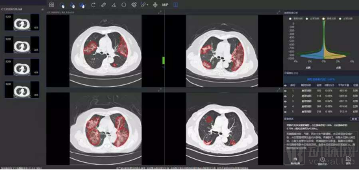

RADLogics的AI软件包括了多种算法,这些算法不仅能够对胸部CT和X光图像检测出异常的部分,还能够自动对病人病情的轻重缓急程度进行分类预警排序,确保放射科医生能及时地对患者进行及时、妥善的检查和治疗。此外,这类基于AI的工具还能对COVID-19疑似患者的肺部CT或X光图像进行量化分析,输出一个相关数值,以便医护人员能对患者不同时间的检查进行对比分析。为了应对此次的新冠肺炎疫情,RADLogics已为不同的临床环境分配了专门的资源,修改算法和部署方式来适应不同的环境,以便实现快速检测新冠肺炎带来的相关的肺部异常影像。这一工具在今年新冠疫情全球肆虐时候,起到关键的辅助筛查作用。

无独有偶,柏视医疗也于疫情爆发的第一时间采取行动,推出了新冠肺炎辅助筛查系统,高效安全地助力病情的诊断与诊疗工作。